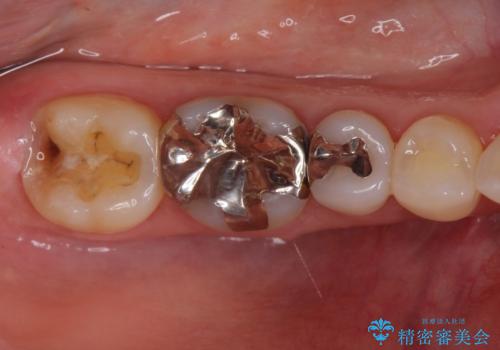

歯ぐきの形を整えることで精度の良い詰め物を入れることができました。

- 右下7 ゴールドインレー 77,000円費用は治療当時の料金となります